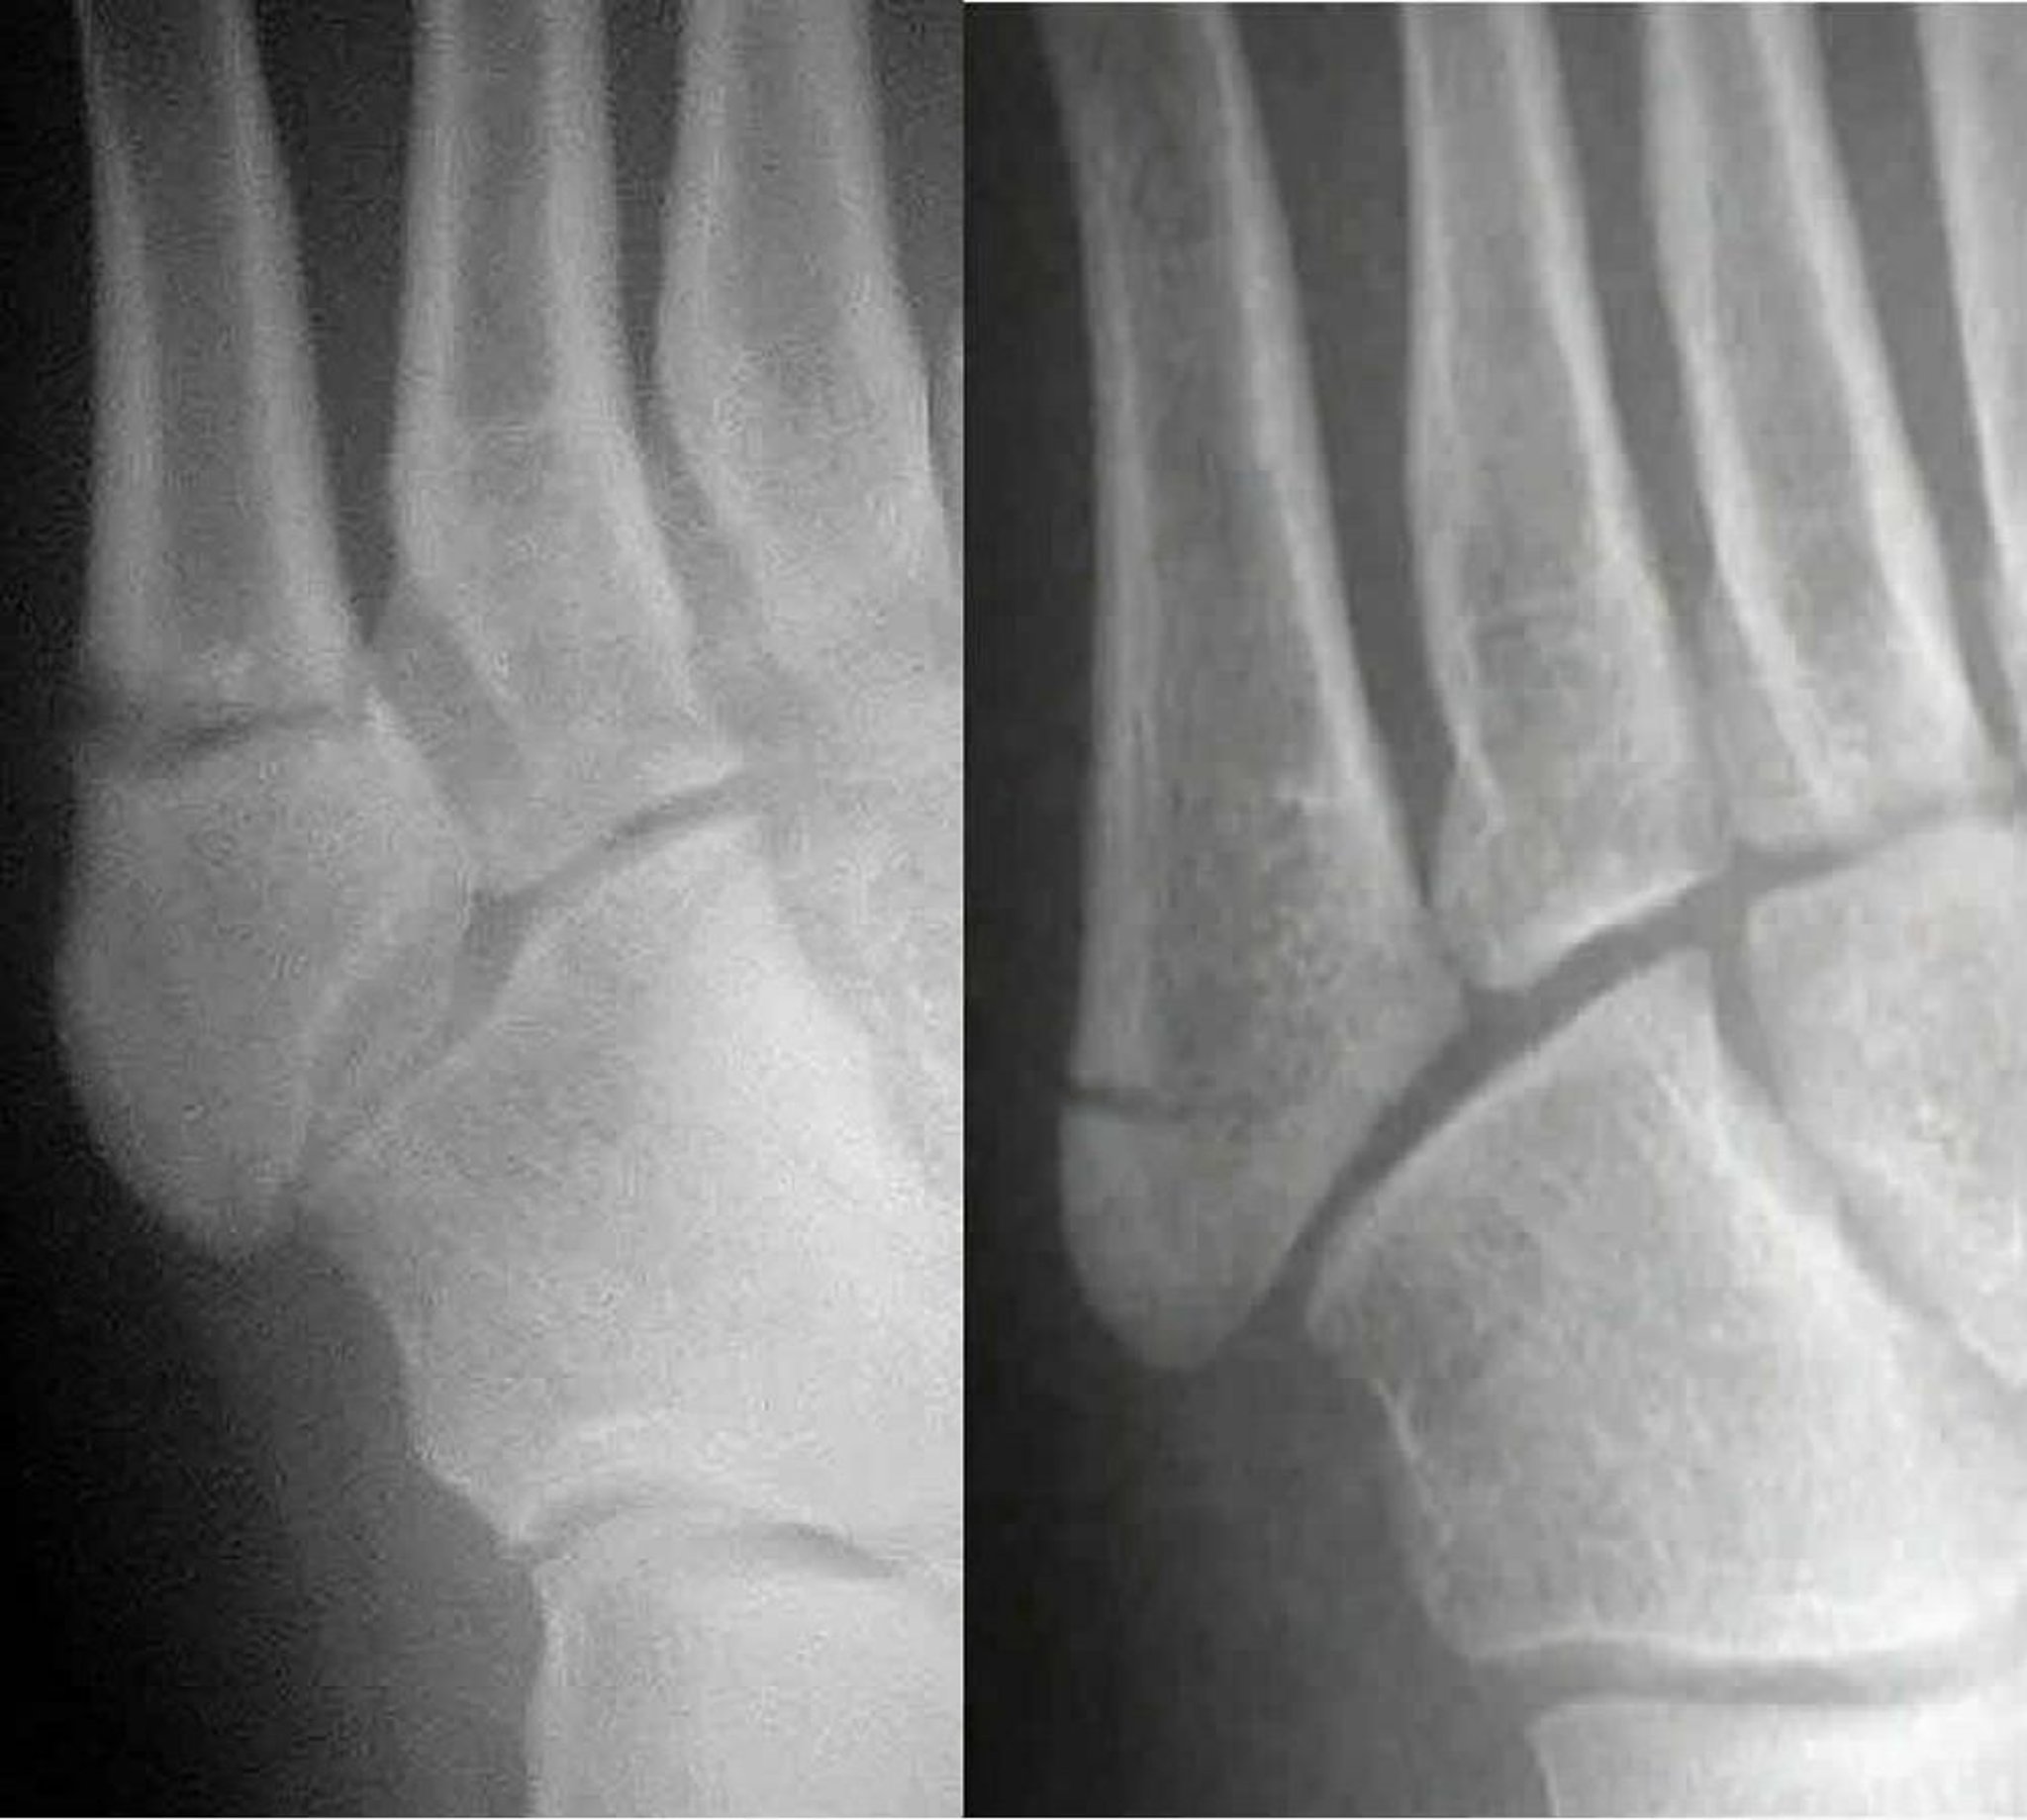

Fractures de Jones versus pseudo-Jones

Une fracture de Jones (à gauche) implique le 5e métatarsien; une fracture pseudo-Jones (à droite) implique la base du 5e métatarsien. Distinguer les deux est important car elles sont traitées différemment.

Images courtesy of Danielle Campagne, MD.